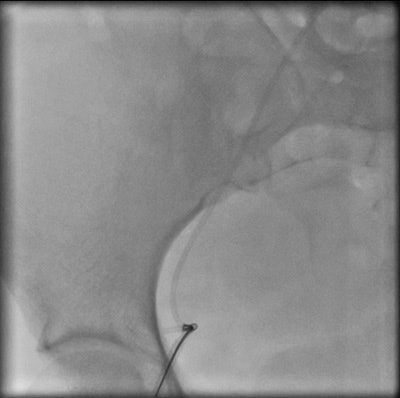

Chest radiograph of a 32-year-old woman shows cardiac migration of the proximal fragment of a fractured portacath. All images courtesy of Drs. Jamal Al Deen Alkoteesh and Maysam T. Abu Sa'a.The portacath fracture was incidentally discovered on chest radiograph, which showed cardiac migration of the proximal fragment. Echocardiography was performed and showed preserved left ventricular function with ejection fraction of about 50% to 55%. No regional wall motion abnormalities seen. Linear shadow was seen on echocardiography, representing the retained fragment.

Percutaneous retrieval of the retained fragment of the fractured portacath catheter was successfully accomplished on the second attempt. Following prepping of the right groin, the right femoral vein was punctured and an 8 French sheath was inserted. Selective catheterization of the right ventricle was performed using a 6 French catheter. A 25-mm snare was used to capture the migrated retained fragment. It was then removed successfully without immediate complications.